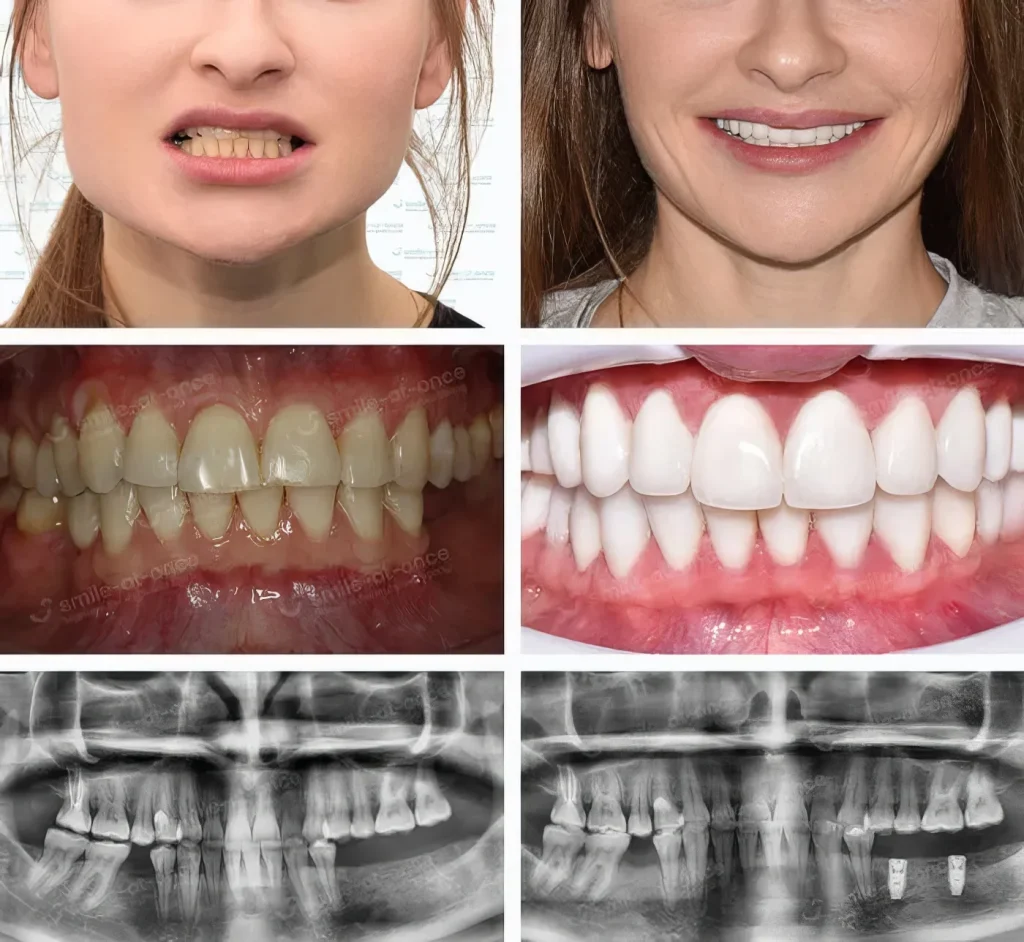

Истории из практики (чтобы было «как в жизни», а не «как в учебнике»)

Случай 2. Стираемость и «кислотная» эмаль

Андрей, 36 лет, часто пил газировку плюс имел ночной бруксизм: эмаль истончена, края «пожеваны». Цель — восстановить длину и закрыть трещинки. Здесь виниры работают надежнее: мы спроектировали форму, настроили окклюзию, подобрали сплинт-терапию на ночь. Через неделю Андрей сказал, что перестал «стесывать» зубы и улыбка стала «собранной».

Случай 3. Выраженная пигментация и требовательность к оттенку

Ольга, 37 лет, педагог: выраженная пигментация после кофе/чая, плюс сколы. Хотела «эффект реставрации эмали», но без «фарфоровой улыбки». Мы сделали эстетическую диагностику, цифровой проект, подобрали виниры E.max с естественной прозрачностью режущего края.